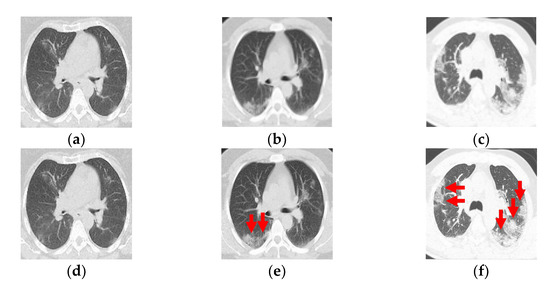

2.2. Ground-Glass Opacity and Pulmonary Infiltrates Highlighted by Saliency Fusion

3.2. Quantitative and Qualitative Evaluation of PP and GGO–PI Identification